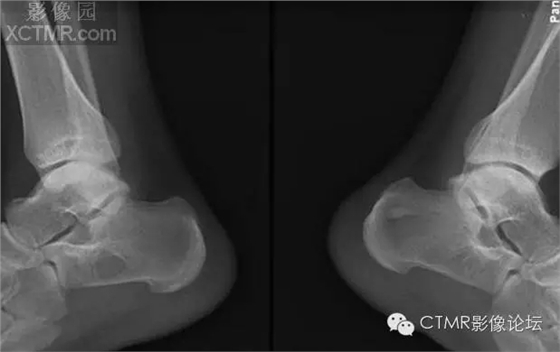

骨髓竇是指松質(zhì)骨內(nèi)先天性骨小梁發(fā)育稀少,各組骨小梁間的骨小梁少或缺如,形成一空腔,內(nèi)含有骨髓,稱為骨髓竇,為正常解剖變異。骨髓竇以跟骨最多見(jiàn),簡(jiǎn)稱骨髓竇,其次見(jiàn)于股骨頸、股骨遠(yuǎn)端及髖臼上緣等處。

【臨床表現(xiàn)】

成人多見(jiàn),因系解剖變異,無(wú)癥狀。常因外傷或其他原因做X線檢查時(shí)發(fā)現(xiàn)。

【X線表現(xiàn)】

1.跟骨竇的形成 跟骨示足弓的重要支點(diǎn),承受著來(lái)自自身及負(fù)荷的重量。為了適應(yīng)承受重量的力學(xué)需要,跟骨的結(jié)構(gòu)十分精密合理。其骨小梁的發(fā)育有三組:①自跟距關(guān)節(jié)后緣向后下方呈斜向走行;②沿跟骨下方分布;③自跟結(jié)節(jié)處向前方伸展。三組骨小梁間有一個(gè)類三角形、圓形或橢圓形透亮區(qū),即跟骨竇。

2.跟骨竇的表現(xiàn) 觀察跟骨竇以側(cè)位平片為佳。其特點(diǎn)是位于跟骨前部中央,跟骨溝后方,尖端向上,足弓后上部,承受重量輕的特定位置。竇的基底與跟骨下緣平行。與竇基底相當(dāng)?shù)母窍戮壠べ|(zhì)密度高,呈致密帶狀或線狀。竇內(nèi)骨小梁稀少或缺如。邊緣清楚整齊,無(wú)硬化。大小1-3cm。竇內(nèi)有時(shí)可見(jiàn)營(yíng)養(yǎng)溝。多數(shù)為單側(cè),少數(shù)雙側(cè)對(duì)稱發(fā)生。竇周骨質(zhì)正常。

【鑒別診斷】

1.跟骨囊腫 囊腫多位于跟骨后中部,與跟骨竇位置不同。呈圓形或橢圓形,囊內(nèi)無(wú)骨小梁,高度透亮,膨脹生長(zhǎng),周邊輕度硬化。

2.單房性巨細(xì)胞瘤 破壞區(qū)邊緣清楚,內(nèi)無(wú)骨間隔。骨皮質(zhì)變薄。臨床上有疼痛。腫瘤多位于跟骨后部,腫瘤中心多在跟骨竇之后。

3.跟骨結(jié)核 病變范圍較小,病變呈不規(guī)則破壞,邊緣模糊,無(wú)硬化,周圍骨質(zhì)疏松。

4. 骨內(nèi)脂肪瘤 骨內(nèi)脂肪瘤極罕見(jiàn),多在長(zhǎng)骨干骺。x光片見(jiàn)膨脹镕骨破壞,周邊光滑,有硬化緣,有時(shí)有鈣化灶,可誤診為骨梗死。病理:巨檢 黃色質(zhì)軟,脂肪祥,可鈣化或囊性變。

骨髓竇是指松質(zhì)骨內(nèi)先天性骨小梁發(fā)育稀少,各組骨小梁間的骨小梁少或缺如,形成一空腔,內(nèi)含有骨髓,稱為骨髓竇,為正常解剖變異。骨髓竇以跟骨最多見(jiàn),簡(jiǎn)稱骨髓竇,其次見(jiàn)于股骨頸、股骨遠(yuǎn)端及髖臼上緣等處。X線表現(xiàn)邊緣清楚整齊,無(wú)硬化,大小1-3cm,病變區(qū)內(nèi)無(wú)鈣化,竇內(nèi)有時(shí)可見(jiàn)營(yíng)養(yǎng)溝。竇周骨質(zhì)正常。